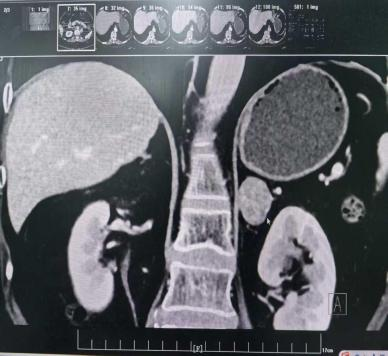

王女士的诊疗充分展现了附属医院在应对此类复杂病症时的专业与精准。她患高血压多年,规律服用多种降压药仍难以控制,还新增尿频尿急症状。文永安主任接诊后,敏锐察觉潜在病因,立即组织团队进行全面评估:细致梳理病史、制定针对性检查方案,最终通过肾上腺CT与内分泌检测,确诊为“肾上腺占位性病变”,且肿瘤有分泌功能,这正是血压居高不下的根源。

明确病因后,手术成为关键。考虑传统开放手术创伤大、恢复慢,结合王女士身体状况,泌尿外科团队决定实施腹腔镜微创手术。术中,凭借娴熟技巧与默契配合,在高清腹腔镜下精准分离肿瘤,最大程度保护周围器官。手术创伤小、出血少,术后王女士血压稳步降至正常,尿频尿急症状消失,无需再依赖多种降压药。

以下几种人群需警惕:50岁以下初发高血压者;长期服药仍难控血压者;血压短期骤升、舒张压超130mmHg者;伴向心性肥胖、心悸出汗、严重打鼾者。针对肾上腺肿瘤,泌尿外科团队会个性化施治:<3cm无功能肿瘤定期随访;>3cm无功能肿瘤建议微创切除;有功能肿瘤无论大小,多需腹腔镜切除,术后多数人血压改善。